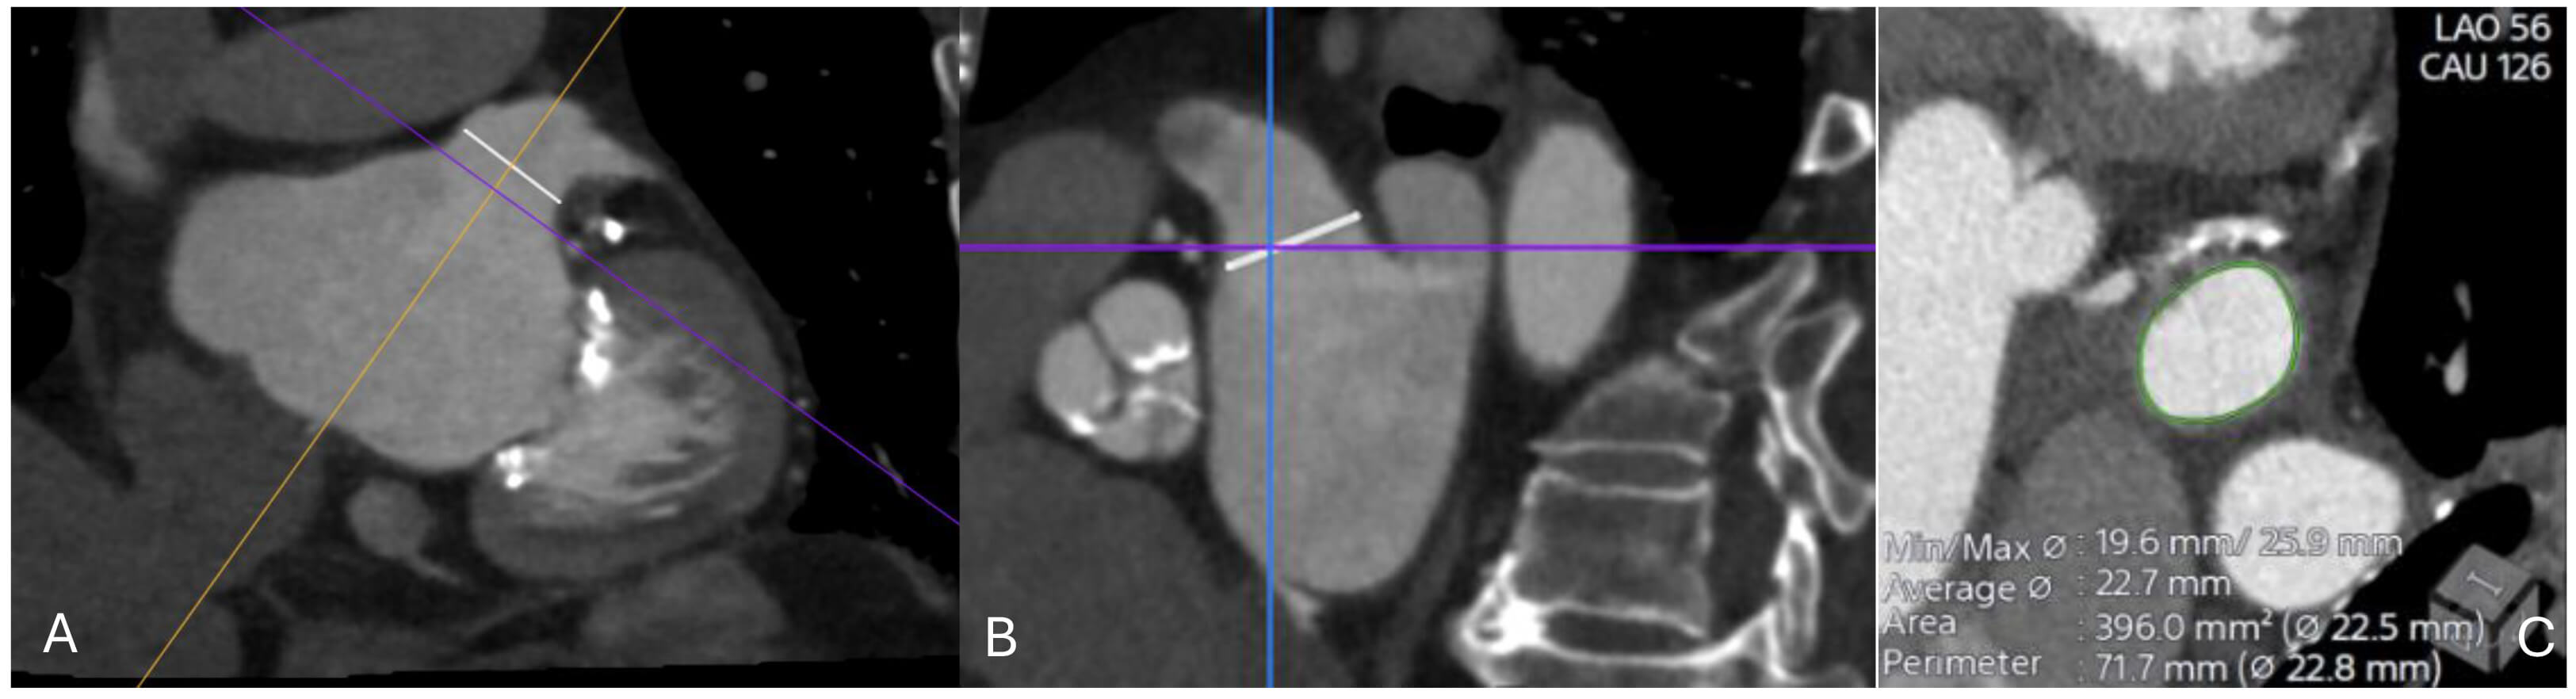

The first step in pre-procedural evaluation is exclusion of LAA thrombus. TOE remains widely used for this purpose, but contrast-enhanced CT with delayed imaging (typically 60–90 seconds post-contrast) has demonstrated high sensitivity and specificity for differentiating thrombus from slow flow. CT is particularly valuable for characterizing LAA morphology. It allows classification into common morphotypes (chicken wing, windsock, cactus, cauliflower), which have been linked to procedural feasibility and risk of residual leaks. CT characterizes LAA morphology and landing-zone geometry, as summarized in Tables 4,5 [111]. These measurements directly inform device sizing (Fig. 7). For example, the Watchman FLX typically requires oversizing of 10–20% relative to landing zone diameter, while the Amplatzer Amulet requires assessment of both ostial and landing zone diameters for appropriate sizing. Peripheral access evaluation is also essential, particularly in patients with peripheral vascular disease. CT allows assessment of iliofemoral access in the same dataset used for cardiac anatomy.

Fig. 7.

CT imaging assessment of the left atrial appendage (LAA) prior to percutaneous closure. (A) Oblique multiplanar reconstruction demonstrating the ostium of the LAA (white line), aligned along the true anatomical axis. (B) Orthogonal cross-sectional view showing the same ostial measurement (white line) in the perpendicular plane. (C) Cross-sectional reconstruction at the level of the ostium with automated contouring (green) and derived measurements of minimal and maximal diameters, average diameter, area, and perimeter (22.5–22.8 mm). These values are used for device sizing and procedural planning.